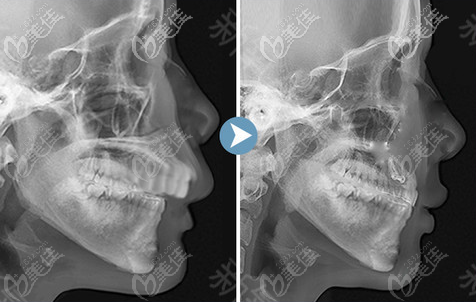

上顎骨突出矯正手術(shù)屬于四級頜面整形手術(shù),具有一定的風(fēng)險,為了降低手術(shù)風(fēng)險,建議選大型正規(guī)具備四級頜面磨骨資質(zhì)的醫(yī)院和醫(yī)生進(jìn)行手術(shù)。